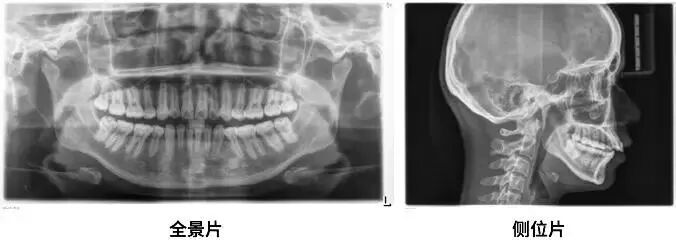

1.X 光片帮助医生判断你的牙齿情况

通过这两张片子,医生能够对你的牙齿、牙根、牙槽骨、颌骨甚至关节等进行判断、数据分析,就像这样发现一堆肉眼无法发现的问题!